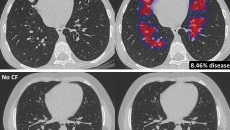

The new algorithm allows for automated analysis of CT scans of patients with the condition.

By Sara Mageit | 08:10 am | October 16, 2020